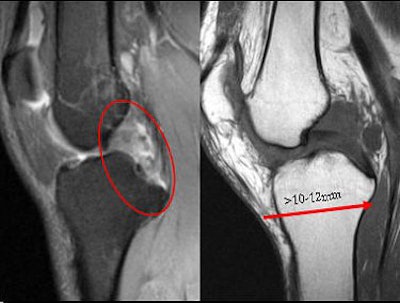

Beall pointed out that PCL reconstruction is an effective treatment method for an injured PCL, but controversy remains over repair versus conservative treatment. Unlike the ACL, even severe PCL injuries have been known to heal fairly quickly. But debate continues over a correlation between the location of the PCL injury and its propensity for healing. A PCL tear may be less likely to heal under the following conditions, Beall said:

- Complete tear of the anteriolateral and posteromedial bundles

- Associated MCL/posterolateral corner injury

- Post-translation greater than 10-12 mm on stress radiography

As for the PCL, "PCL (injuries) will heal even if they are complete," Beall said. "Which tears don't heal? The ones with medial or lateral complex injuries, and tears that are associated with 10-12 mm or more posterior drawer."